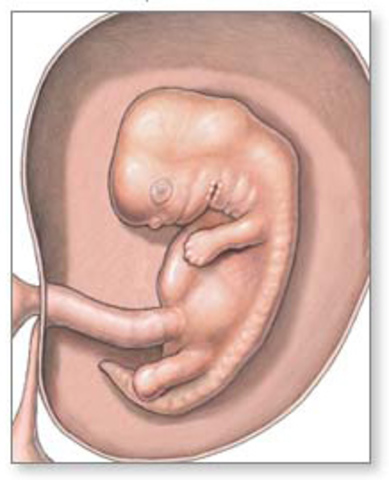

• SEGUNDA SEMANA

SEGUNDA SEMANA

A partir de la semana 2 de embarazo, se desarrolla lo que llamamos embrión, que tiene básicamente una cabeza, un tronco y una cola rizada.

• DISCO EMBIONARIO TRILAMINAR

DISCO EMBIONARIO TRILAMINAR

Al inicio de ésta semana el disco embrionario, que ahora aparece elongado en sentido cráneo-caudal, presenta una serie de movimientos celulares a nivel del epiblasto, proceso llamado gastrulación, lo que dará origen a las tres capas germinativas del embrión